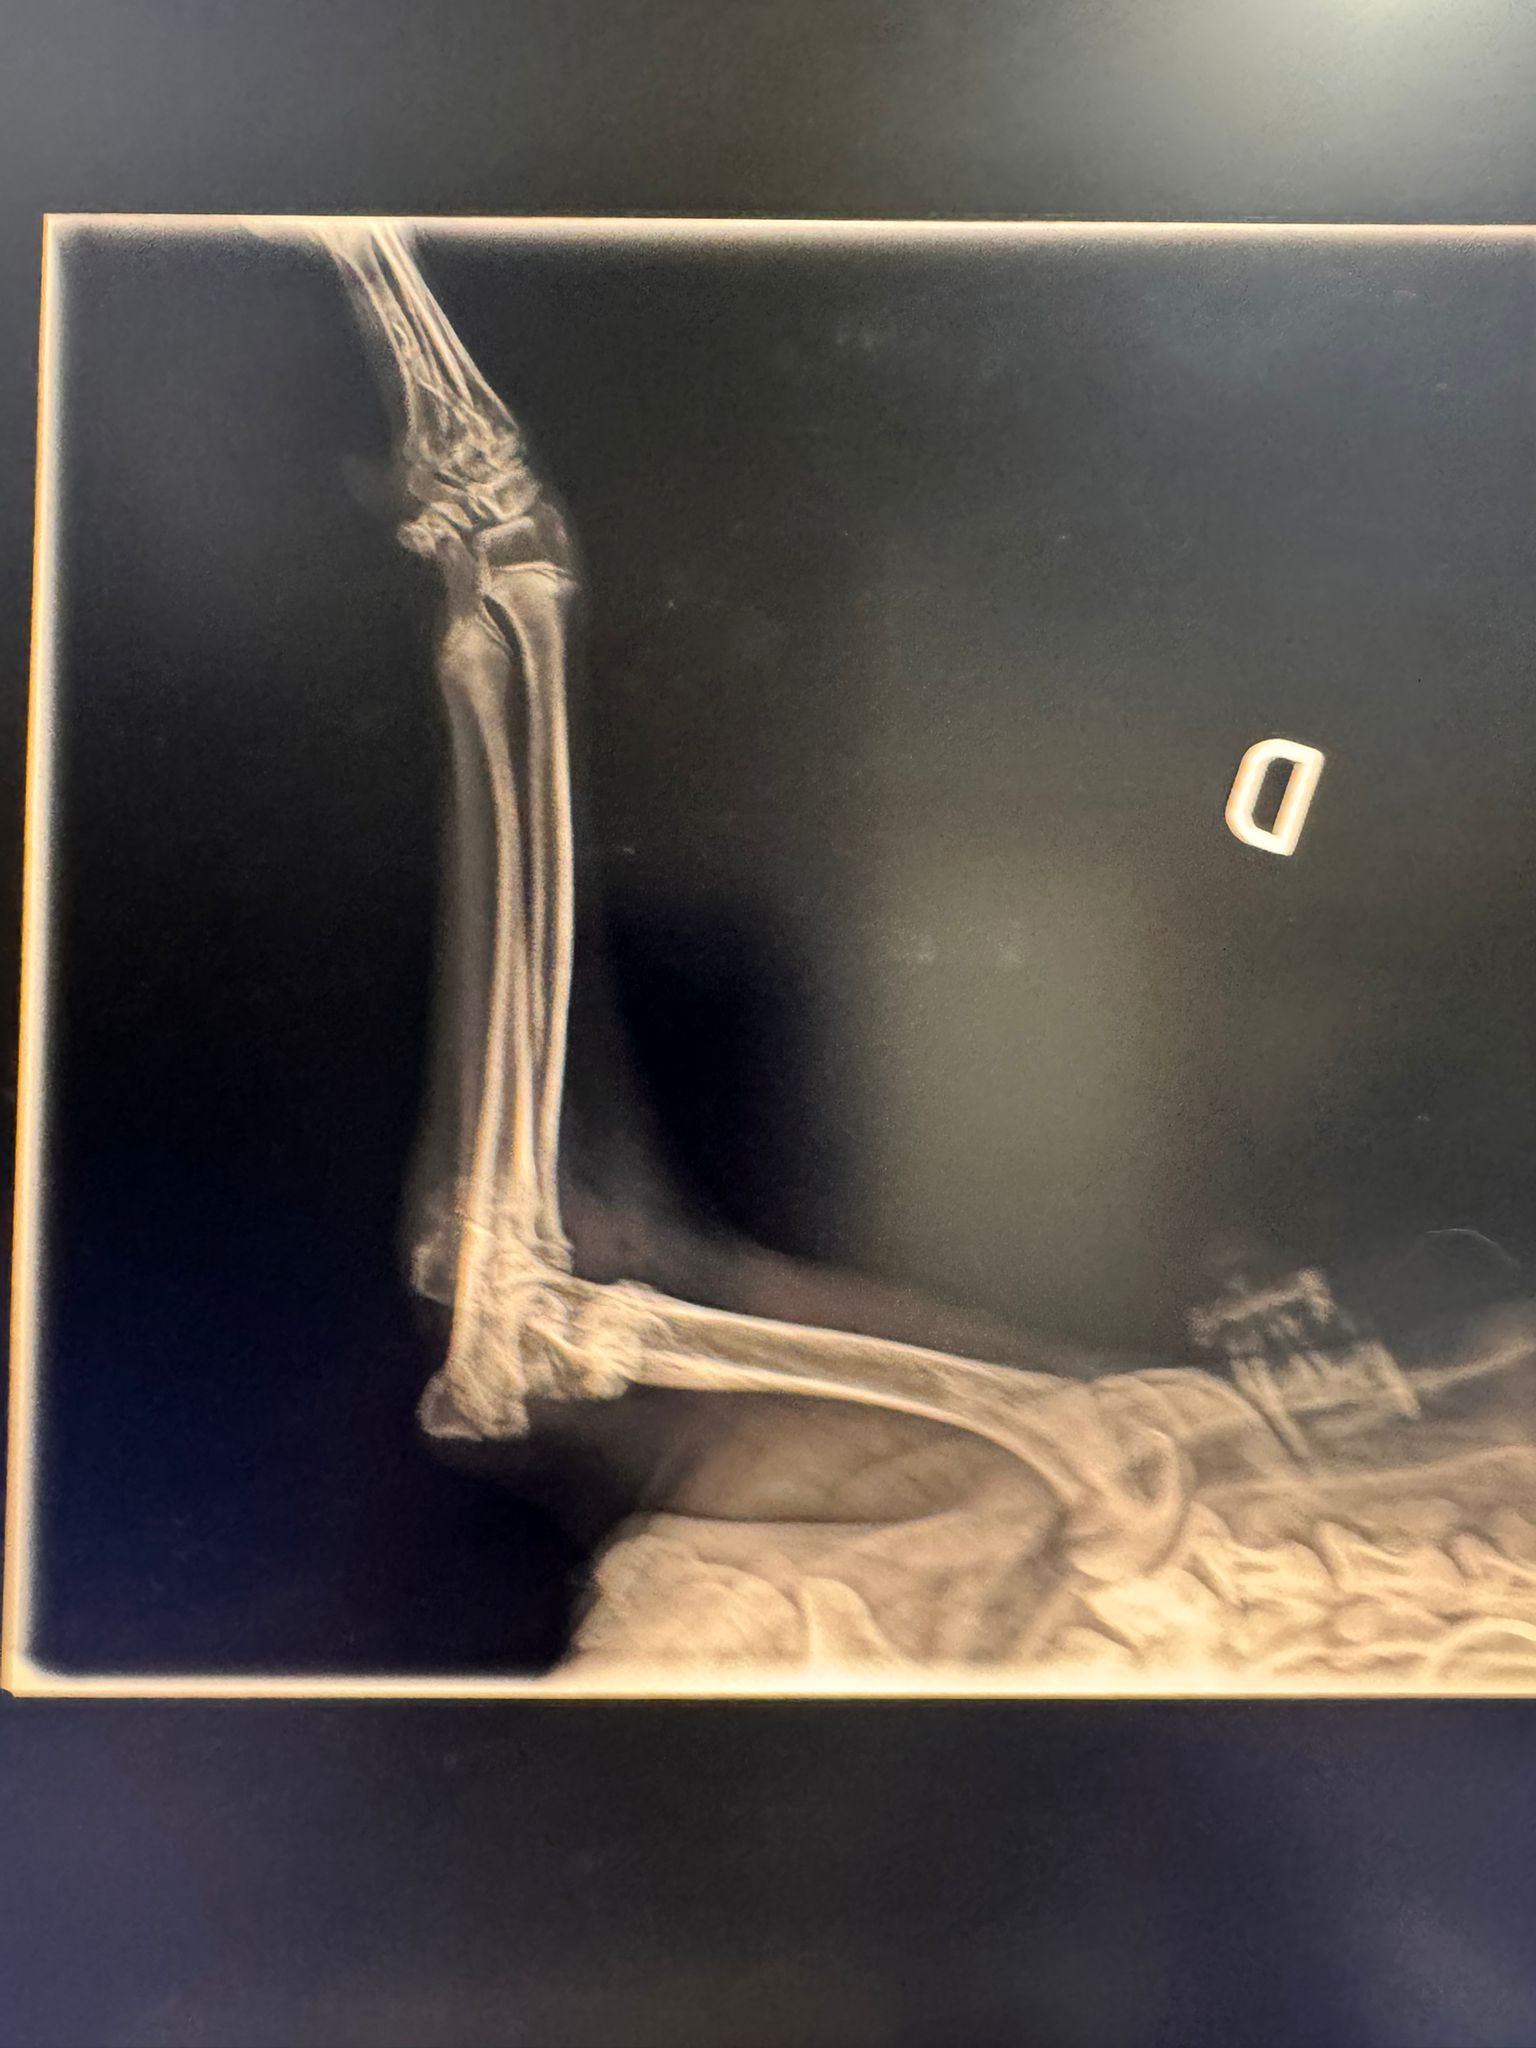

Fractura bilateral de cóndilo lateral, Salter-Harris tipo 4

Y es que Cancho ha sufrido un fuerte traumatismo siendo muy bebé; esto suele pasar cuando caes de una altura considerable. Sus dueños decidieron abandonarlo, la perrera lo recogió y de ahí nos llamaron. Os prometemos que hemos corrido todo lo posible, pero esta vez hemos llegado tarde; no sabemos cuándo fue este golpazo, pero lo que sí sabemos es que ha pasado demasiado tiempo como para poder reparar sus fracturas.

Hoy, durante la cirugía, los pequeños huesos estaban destrozados y llenitos de artrosis. Y no, esta vez tenemos que contaros que no hay reparación posible y que nuestro chico guapo deberá aprender a caminar así.